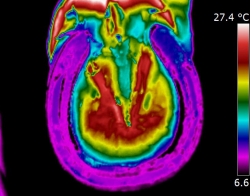

| DISTAL LIMB

| Thermography can point to potential conditions through changes in heat patterns, before the horse shows any clinical signs of injury. It can also reveal hidden signs that other diagnostic tools cannot. It gives us information we didn't know, we didn't know.

| | |  | | | I am very interested in the distal limb and thermography can be used to provide

you and your professional team additional information about conditions such as navicular syndrome,

laminitis, abscesses and corns. Importantly, it can give us information regarding hoof balance and weight-bearing. Hoof balance, often over looked, is a significant influence in the cause of lameness problems not only locally in the foot but throughout the musculature of the body through compensatory issues.